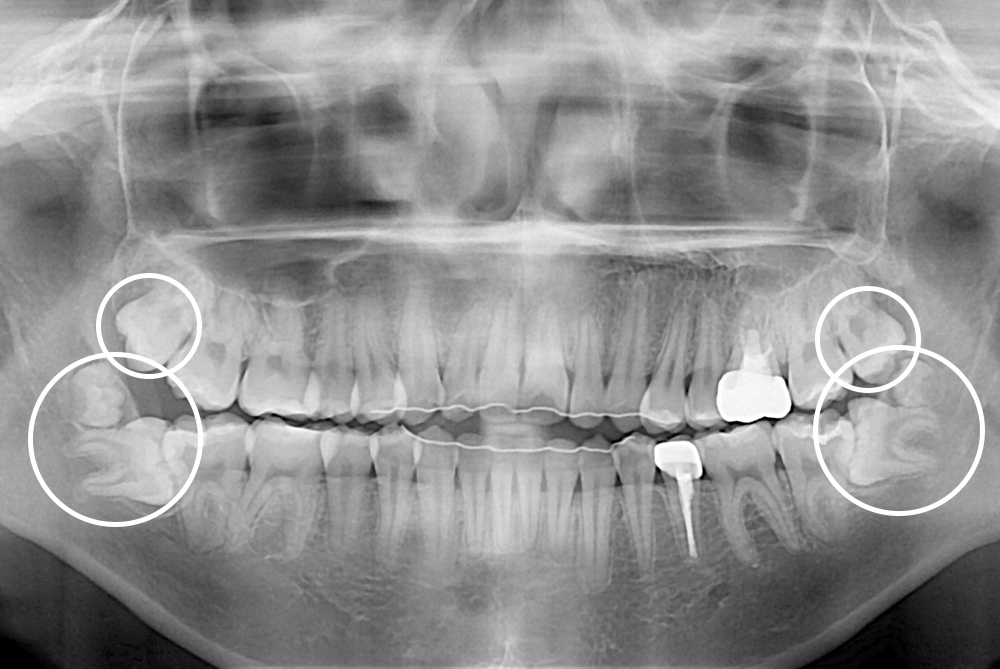

[사랑니] 매복 사랑니 발치

치료전 : 2021-03-02

세종치과는 구강악안면외과학 박사이신 원장님이 발치하는 치과입니다.